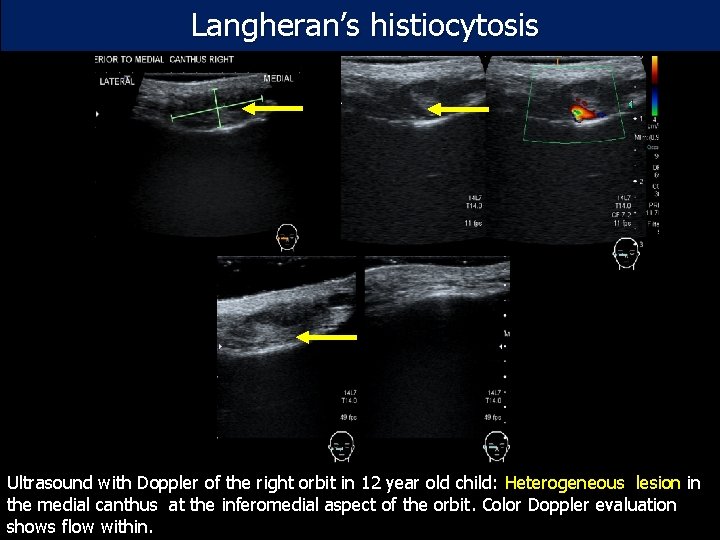

Langheran’s histiocytosis Ultrasound with Doppler of the right orbit in 12 year old child: Heterogeneous lesion in the medial canthus at the inferomedial aspect of the orbit. Color Doppler evaluation shows flow within.